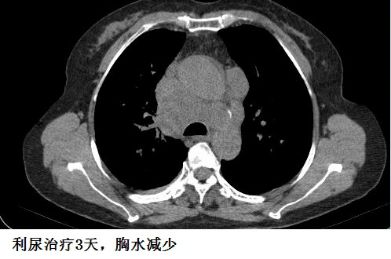

下面的图示,可以帮助大家加深印象!

另外,胸水的病因有时候很难准确判断,最初觉得可能不是心力衰竭引起的,但经验性治疗后,胸水有可能很快减少,这时候贸然按照之前的影像学资料去抽胸水,有可能“干抽”。

这个患者的胸水,应该是心包积液导致静脉回流受阻,体循环淤血引起的。利尿治疗后,胸水减少。

复查CT,“癌性胸水”果然无缘无故减少了。